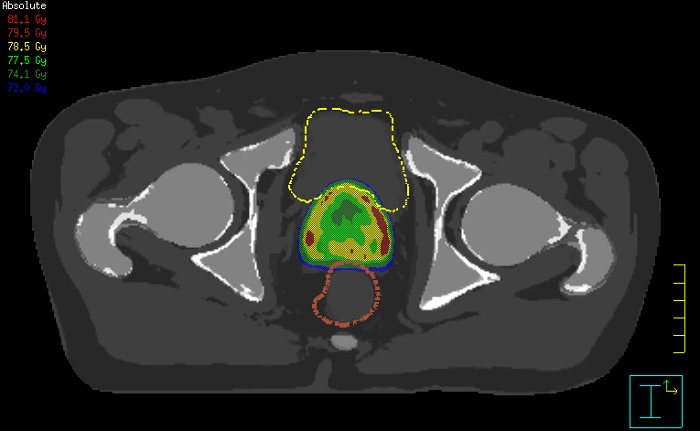

With its exceptional soft-tissue visualization capabilities and wide range of image contrasts, MRI has become a powerful tool to help more precisely define tumor boundaries. This is particularly important as it has been established that there is a high degree of uncertainty in target volume delineation, and it is even reported to represent the largest uncertainty in the entire radiotherapy process for most tumor sites**. Better visualization of the target area and nearby organs-at-risk is a key factor in enhancing target volume delineation. MRI’s expanding role also can be attributed to its functional imaging capabilities, which can inform both target characterization and treatment response.

The ability to tune contrasts can provide even more valuable information about tumor characteristics and tumor extent to facilitate enhanced delineation, and also provides possibilities for dose boosting strategies.

Our innovative MRCAT (MR for Calculating ATtenuation) clinical applications lets you plan radiation therapy using MRI as primary imaging modality. Within just one, fast MR exam, MRCAT provides both excellent soft-tissue contrast for target and OAR delineation and CT-like density information for dose calculations.